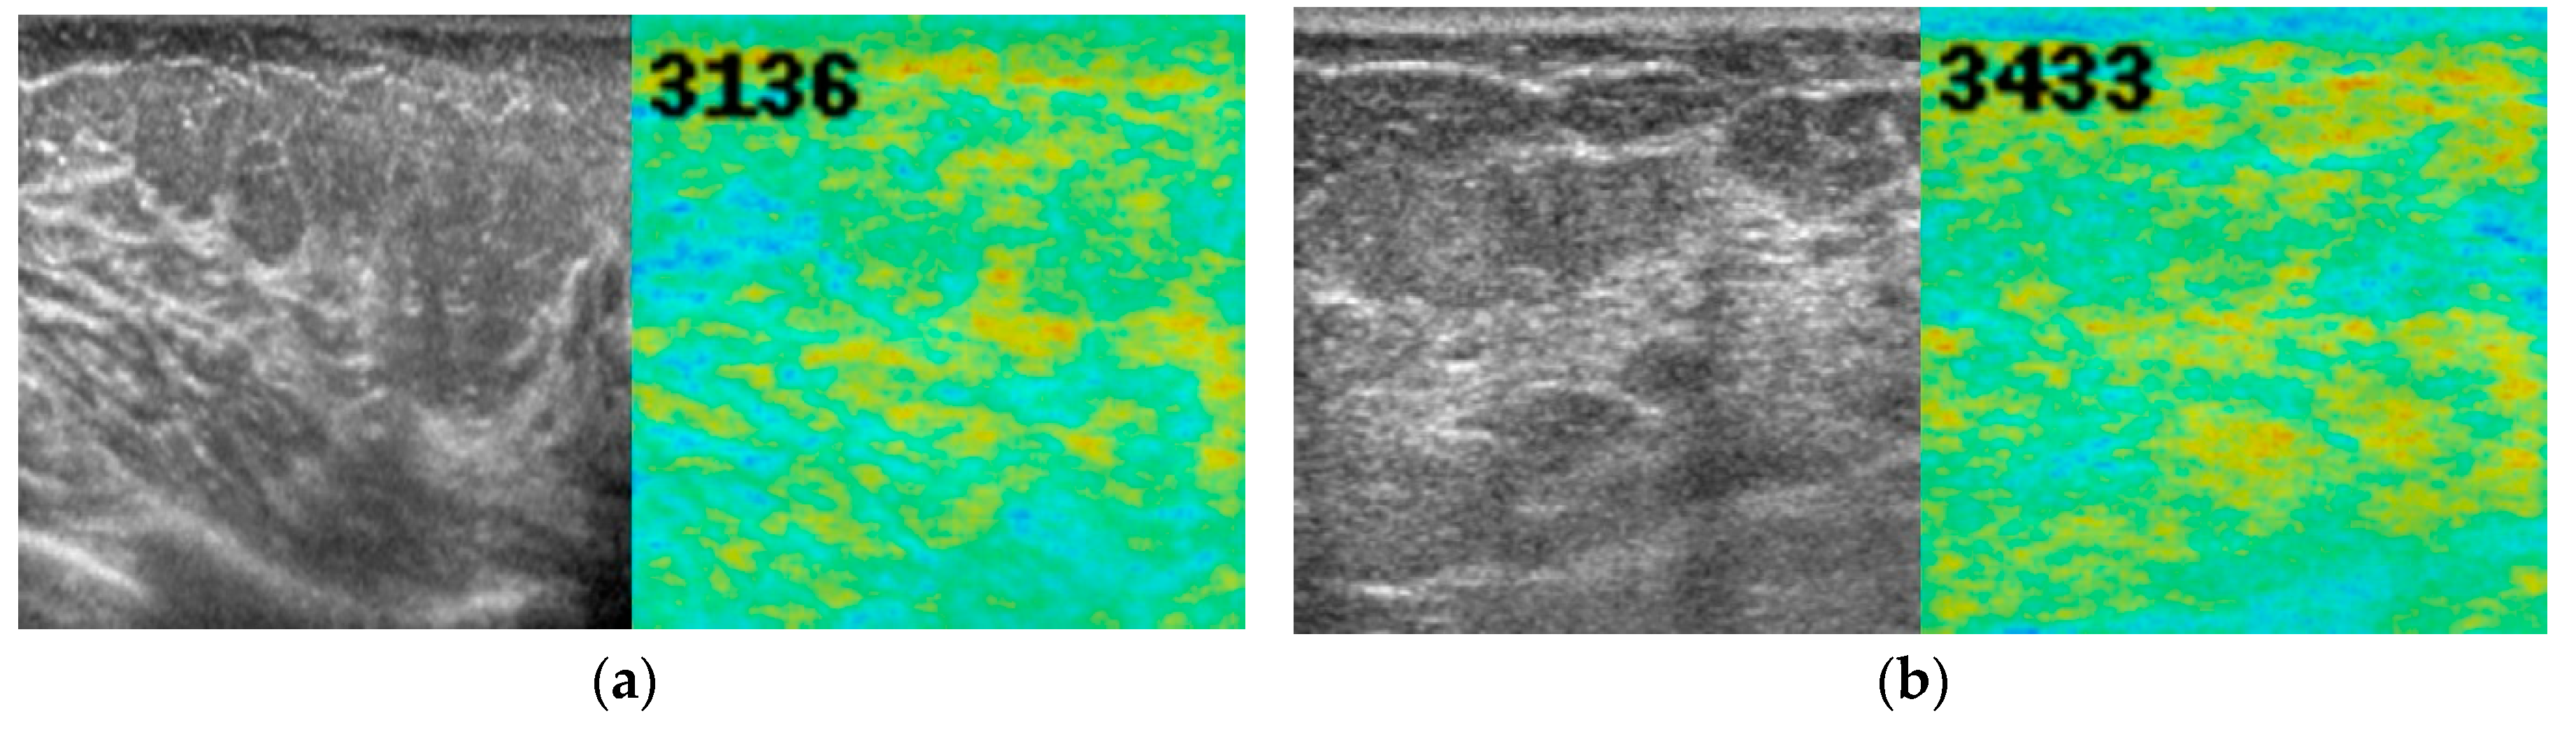

| Normal | 4157.5 ± 418.3 | 3136 | 5021 | <0.001 a | |

| All | 5269.1 ± 1107.2 | 3136 | 8170 | ||